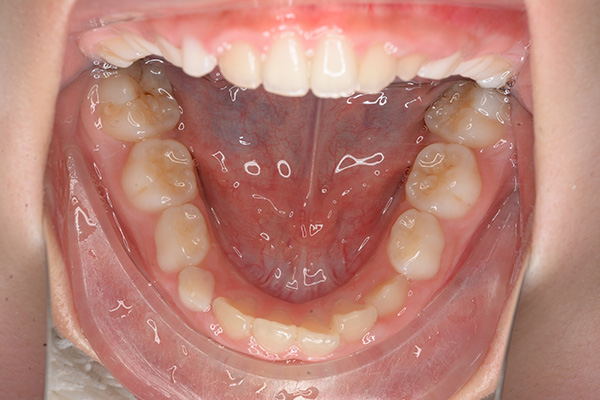

動的治療開始前(9歳7ヵ月)

動的治療開始前

(9歳7ヵ月)

口腔内所見 over jet -2.5mm、over bite 2.0mm、大臼歯関係はⅠ級 。Hellmanのdental ageはⅡCであり前歯部は反対咬合を呈していた。

批評・予后 上顎前歯のアライメントを行ったことで、ロッキングされていた上顎歯槽基底骨の成長に良い影響が生じており、側方歯群の交換も順調に進んでいる症例である。2期治療は相談の上、希望があれば行うこととしている。